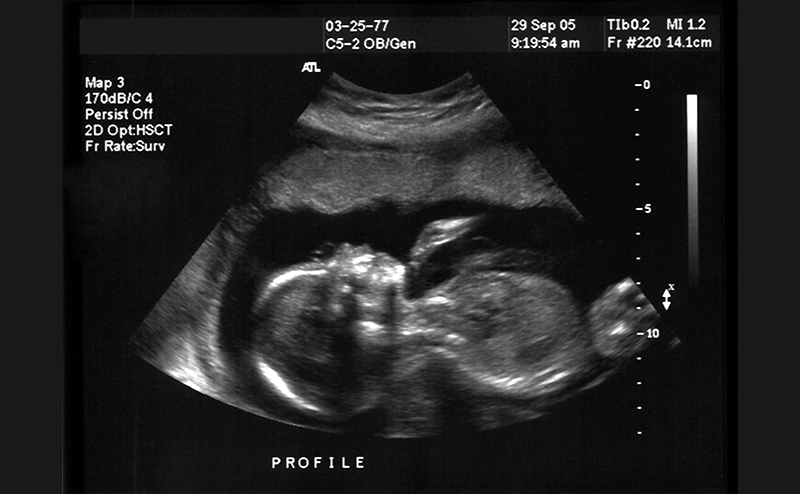

1. Tabbut M, Harper D, Gramer D, Jones R. High-frequency linear transducer improves detection of an IUP in first-trimester ultrasonography. Am J Emerg Med. 2016;34(2):288-291. (subscriber link only)

Summary: In this prospective, single-center convenience sample of 88 first-trimester pregnant patients, 27 of those 88 did not have an IUP visualized transabdominally with a curvilinear probe. 9 of these 27 patients had an IUP visualized with a subsequent transabdominal scan via a linear probe.

This is a 2015 single center-prospective, convenience, pilot study at an academic ED with more than 100,000 patients/year with a residency and ultrasound fellowship. Patients were included if they were in their first trimester of pregnancy, if they had a positive pregnancy test and did not have a prior ultrasound. The majority of images were obtained by an ultrasound fellow or emergency medicine residents during the hours of 8am-5pm due to the presence of an ultrasound team. Philips HD11 or Philips Sparq machines were used.

81 patients were in the final analysis. 54 (66.7%) definitive pregnancies were visualized (1 ectopic) via a transabdominal scan with a curvilinear probe. Of the 27 non-definitive pregnancy locations, 9 patients were found to have an IUP with a subsequent transabdominal scan with a linear probe. Of the remaining 18 patients that needed a transvaginal ultrasound (performed by either radiology or the ED), only 3 had a confirmed IUP.